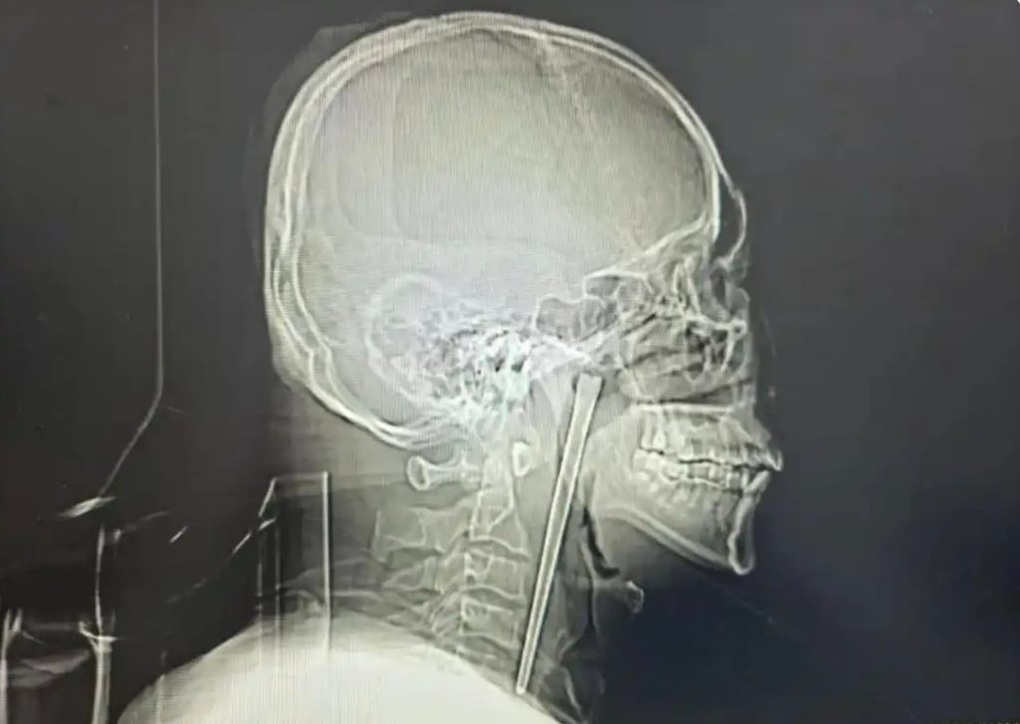

Ảnh chụp X-quang cho thấy vật thể kim loại mắc kẹt trong cổ họng người đàn ông (Ảnh: Alice Yan).

Kết quả thăm khám cho thấy dị vật kim loại nằm ở vùng vòm họng. May mắn là niêm mạc xung quanh không bị tổn thương, các cơ quan liên quan không bị xê dịch và dây thanh quản vẫn hoạt động bình thường.

Bệnh nhân là một người đàn ông họ Wang, sinh sống tại tỉnh Liêu Ninh, phía đông bắc Trung Quốc. Theo thông tin từ cơ sở y tế địa phương, ông đã vô tình nuốt phải một chiếc đũa kim loại dài khoảng 12cm từ 8 năm trước, trong lúc ăn uống có sử dụng rượu.